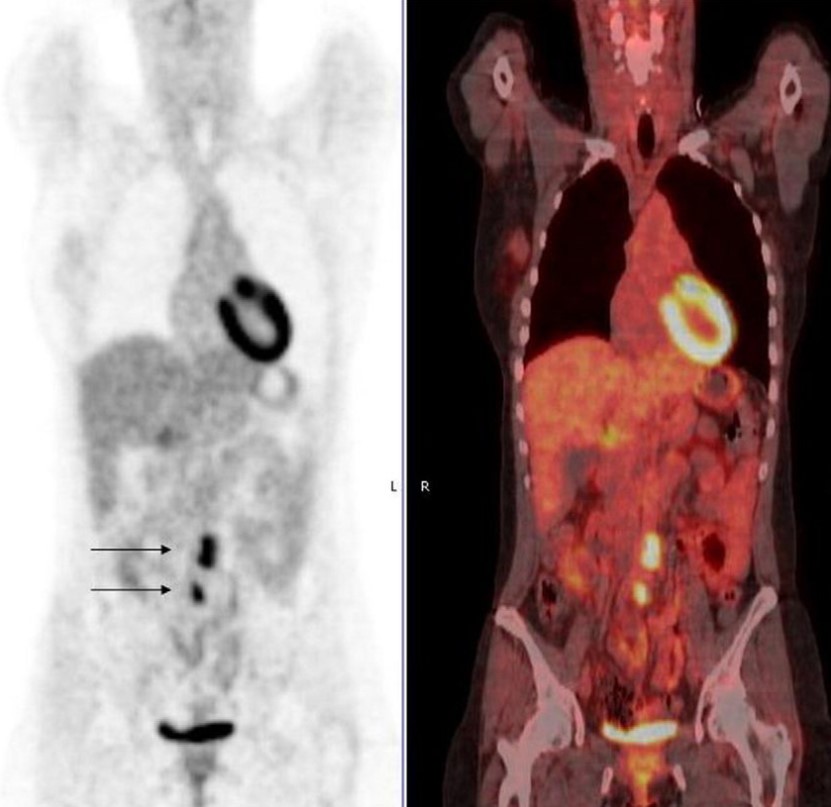

BS.CK1 Cao Thị Lan Hương – bệnh viện Trưng Vương cho biết, vùng cơ tim bị ngủ đông sẽ khiến cho cơ tim bị thiếu máu cục bộ kéo dài. Tình trạng này cần phải được can thiệp bằng nong mạch vành, đặt stent hoặc làm cầu nối để tái tưới máu cho tim.